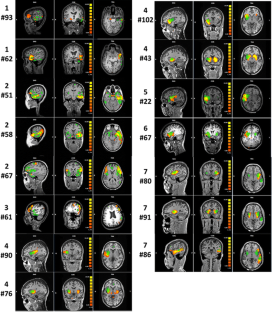

Fig. 3